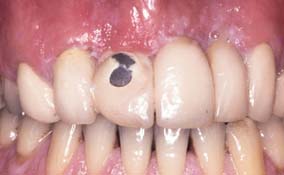

Dental caries (Fig. 32-8) is the most common cause of failure of a cast restoration.9-12 Detection can be very difficult,13 particularly where complete coverage is used. At each appointment, the teeth should be thoroughly dried and visually inspected (Fig. 32-9). The explorer must be used very carefully when early enamel lesions are assessed, because a heavy-handed examination may damage the fragile demineralized enamel matrix. An intact enamel matrix is essential for procedures that induce remineralization14 (e.g., improved plaque control, dietary changes, topical fluoride applications).

Fig. 32-8 Undetected caries beneath this partial fixed dental prosthesis resulted in serious complications.